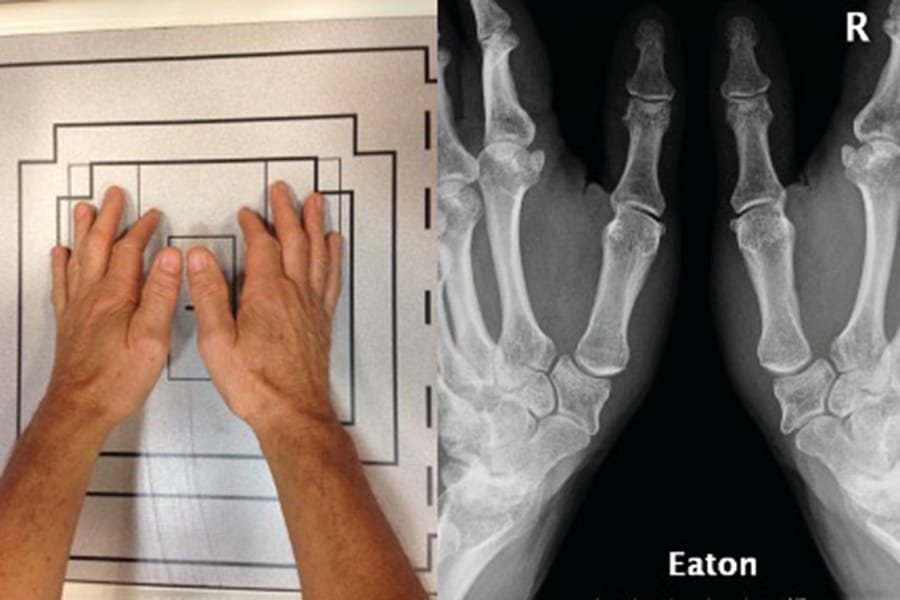

The clinical articles address diverse subspecialties. Trapeziometacarpal joint imaging in the surgical management of basal thumb arthritis informs operative planning in hand surgery, while orthopaedic surgical site infection prevalence in Egypt contributes epidemiological data on infection control. Ligamentous reconstruction is examined through revision ACL reconstruction, and implant selection is explored in the context of short stems for obese patients. The issue concludes with an anatomical and fluoroscopic review of percutaneous screw fixation of the pelvic ring and acetabulum.